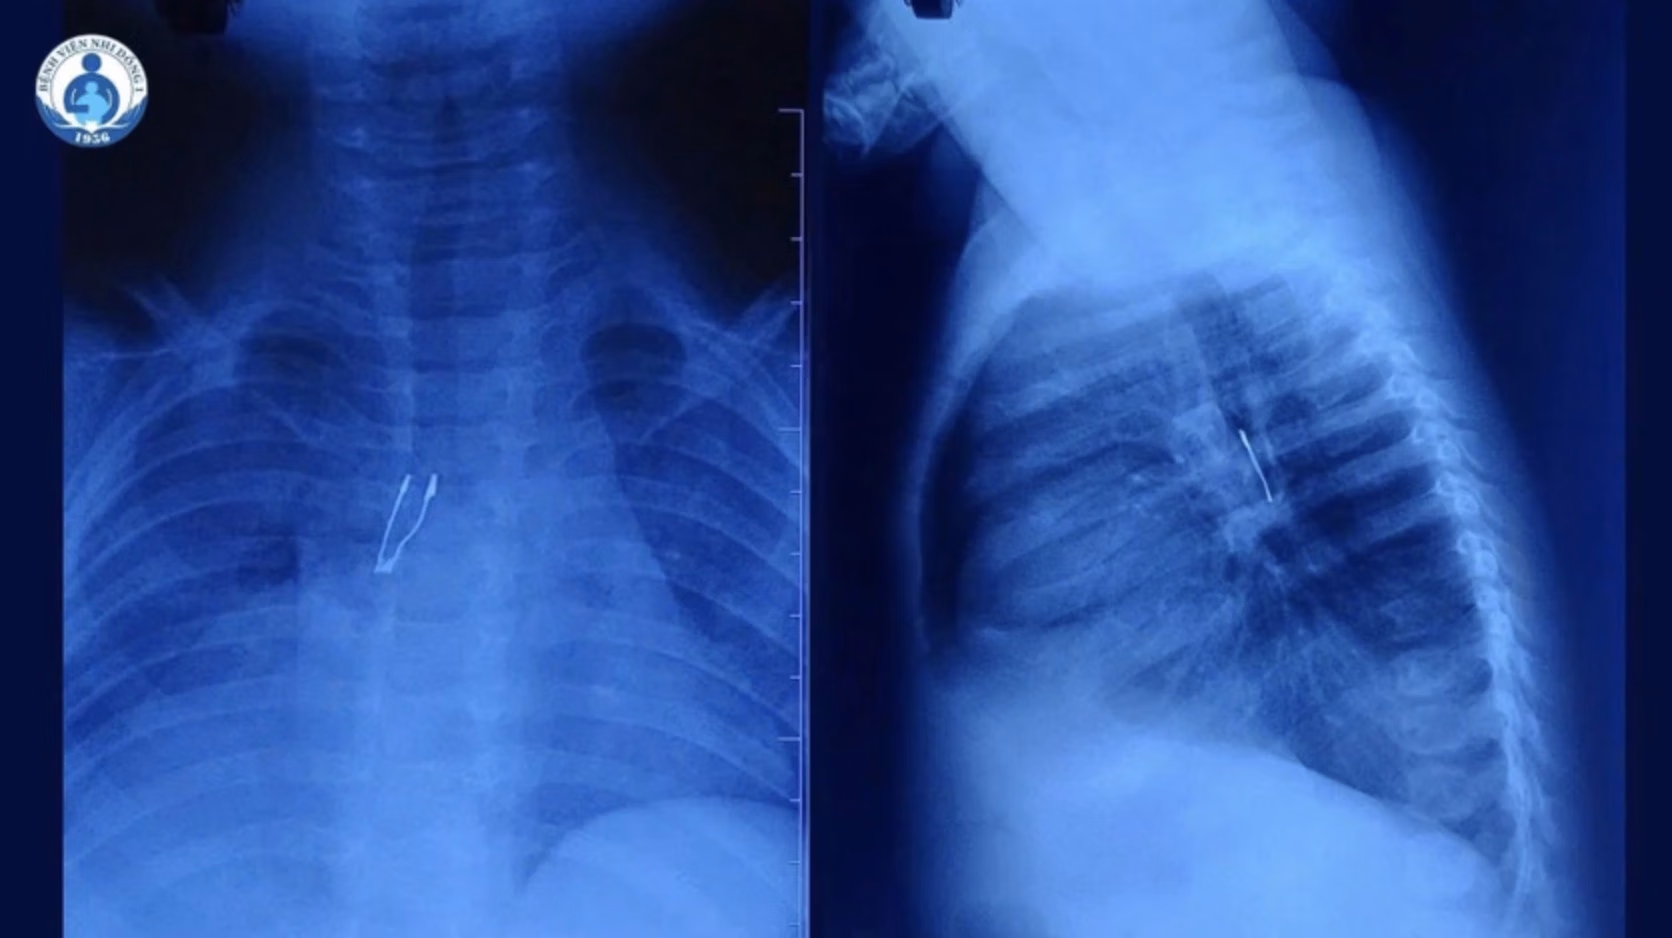

Kết quả chụp X-quang tại bệnh viện cho thấy dị vật cản quang nằm ở phế quản gốc phải, kèm theo tình trạng xẹp phổi phải không hoàn toàn và tràn khí trung thất.

Qua thăm dò, ê-kíp xác định dị vật nghi là một bóng đèn LED mắc sâu trong phế quản gốc phải. Quá trình lấy dị vật gặp nhiều khó khăn do đặc điểm cấu tạo của vật này. Phần đuôi bóng đèn bè to và có cạnh sắc, dễ mắc lại khi kéo qua thanh quản, đồng thời có nguy cơ gây trầy xước, rách niêm mạc hoặc kẹt giữa hai dây thanh.